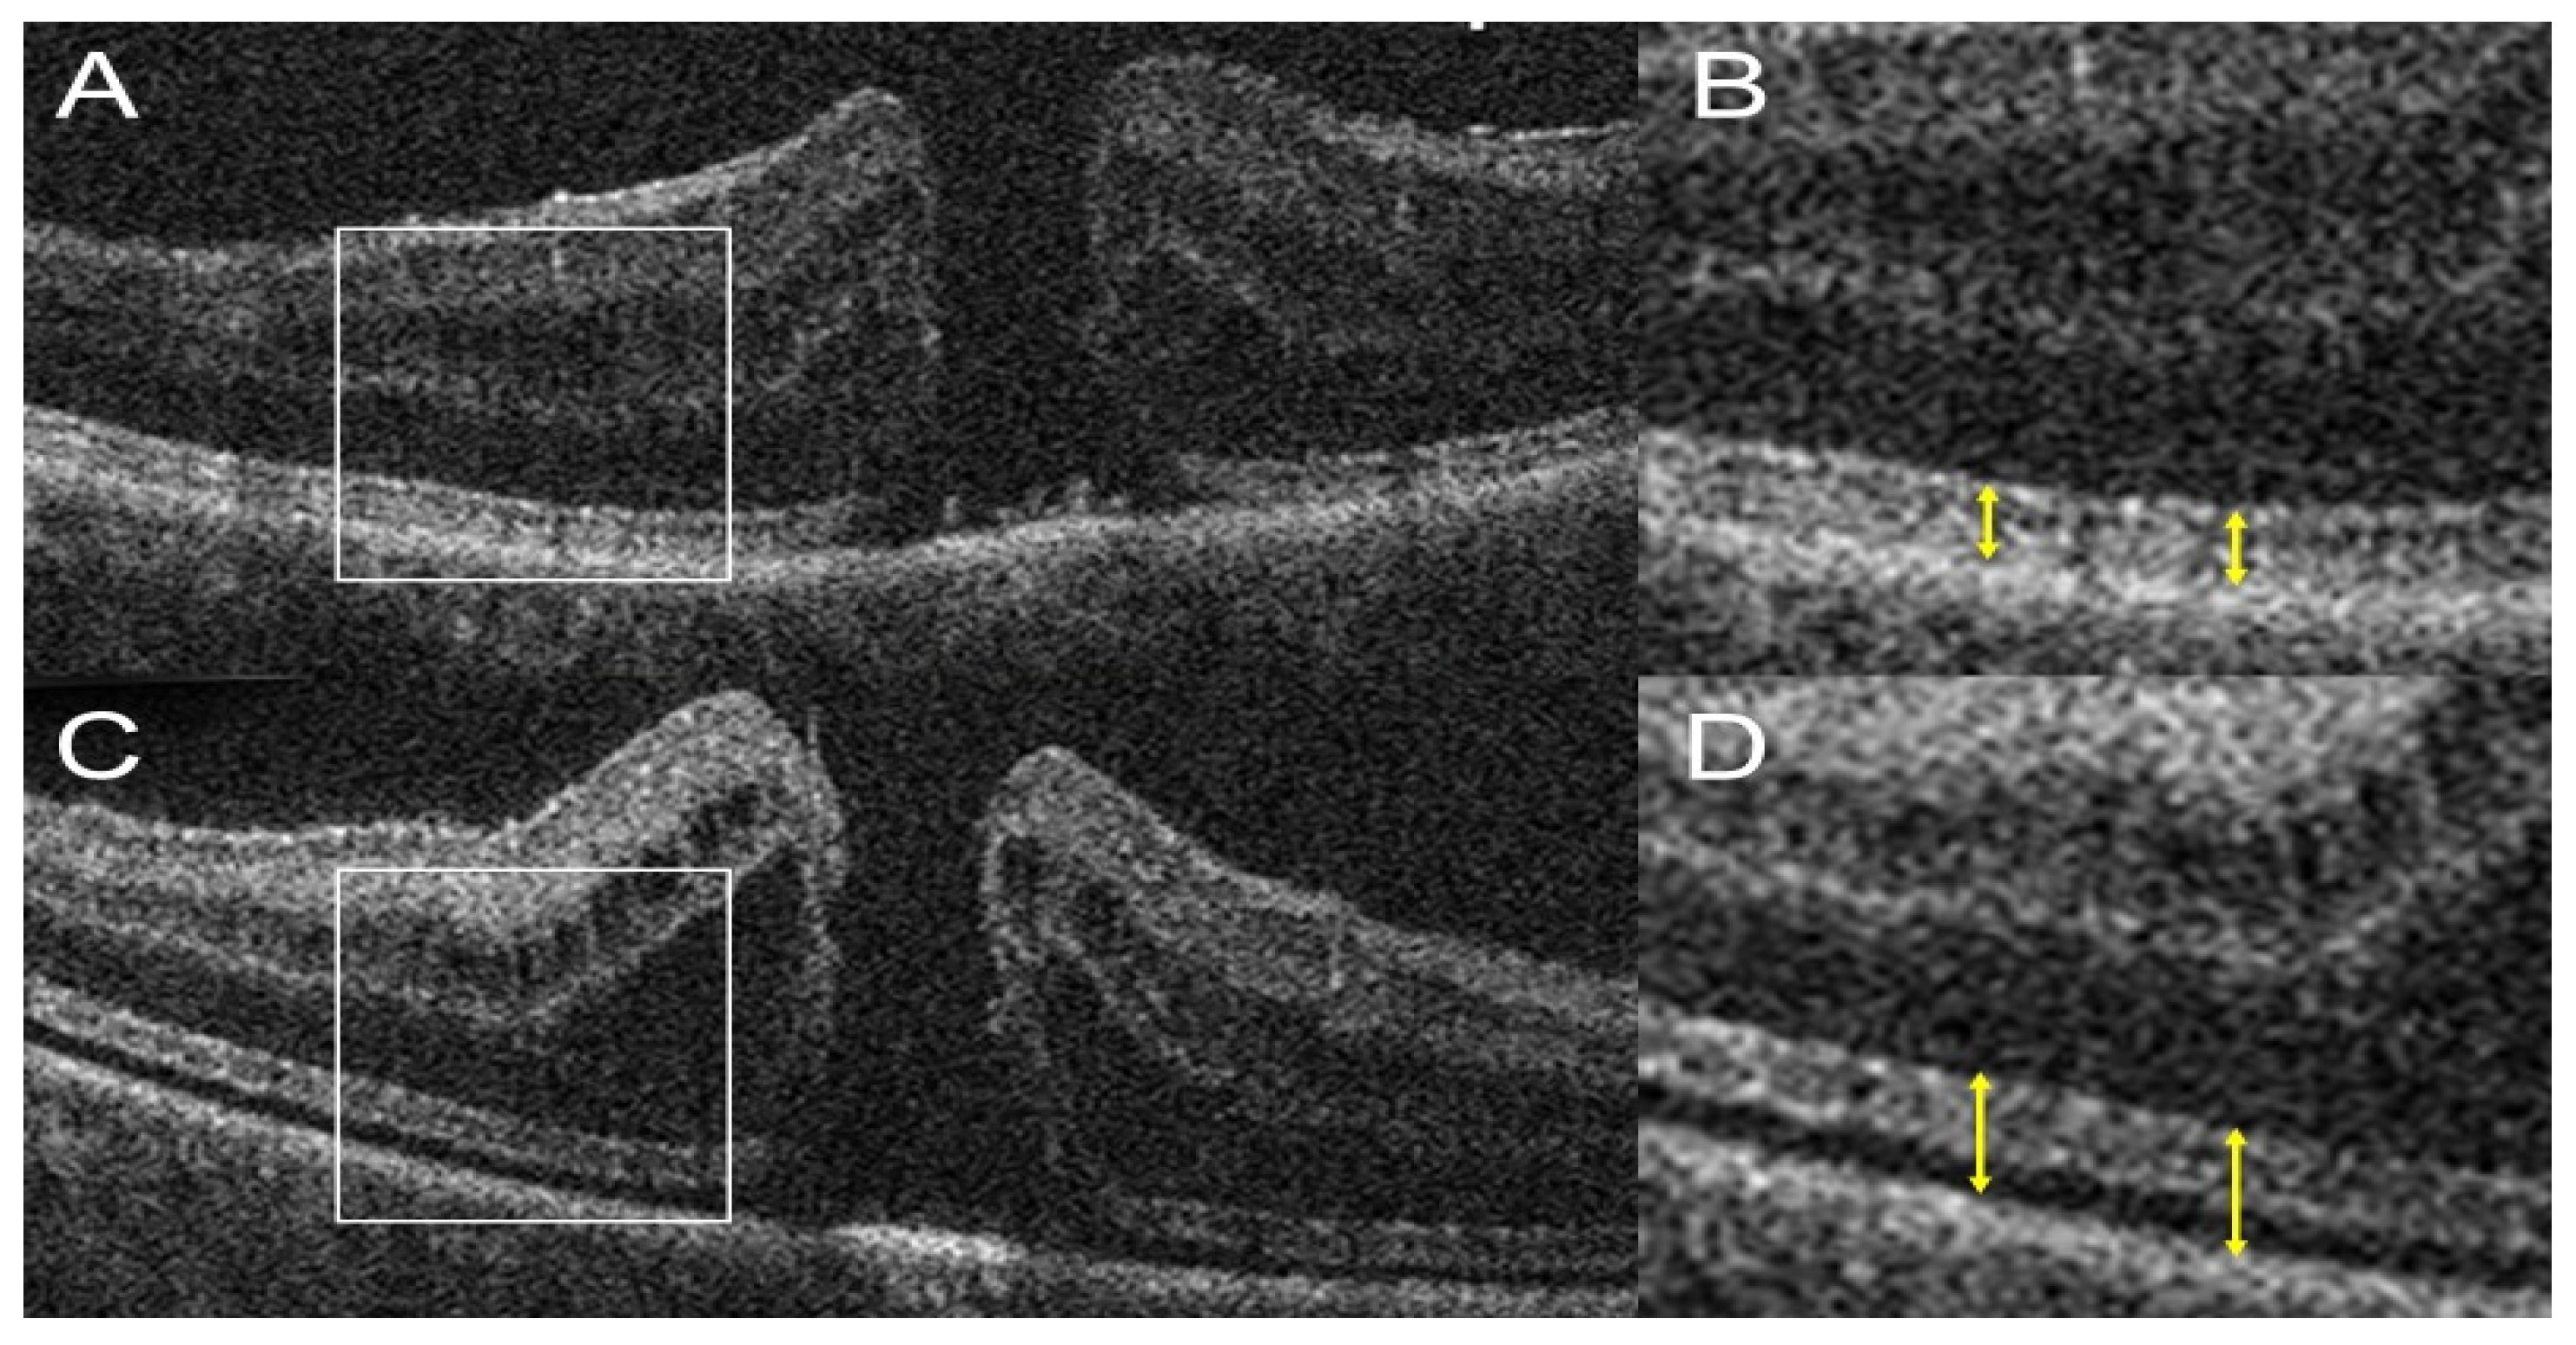

- Keenan, T.D.L.; Goldstein, M.; Goldenberg, D.; Zur, D.; Shulman, S.; Loewenstein, A. Prospective, Longitudinal Pilot Study: Daily Self-Imaging with Patient-Operated Home OCT in Neovascular Age-Related Macular Degeneration. Ophthalmol. Sci. 2021, 1, 100034. [Google Scholar] [CrossRef] [PubMed]

- Maloca, P.; Hasler, P.W.; Barthelmes, D.; Arnold, P.; Matthias, M.; Scholl, H.P.N.; Gerding, H.; Garweg, J.; Heeren, T.; Balaskas, K.; et al. Safety and Feasibility of a Novel Sparse Optical Coherence Tomography Device for Patient-Delivered Retina Home Monitoring. Transl. Vis. Sci. Technol. 2018, 7, 8. [Google Scholar] [CrossRef] [PubMed]